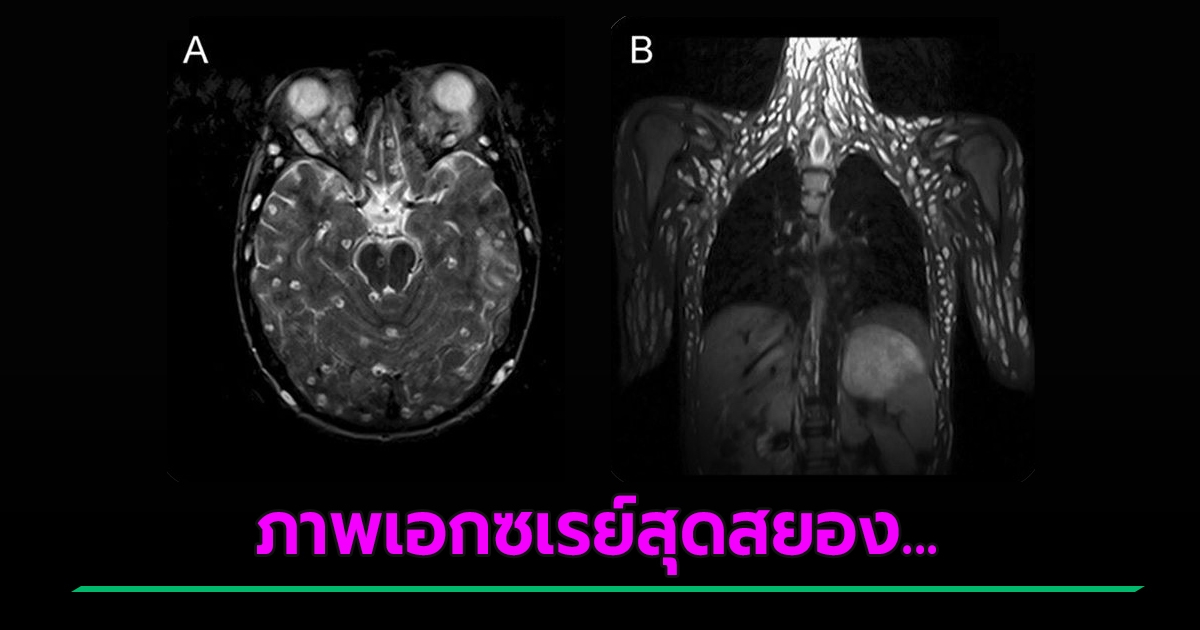

สยองจะเป็นลม ภาพเอกซเรย์คนไข้ พยาธิตืดหมูกระจายทั่วร่าง ลามถึงเนื้อเยื่อสมอง